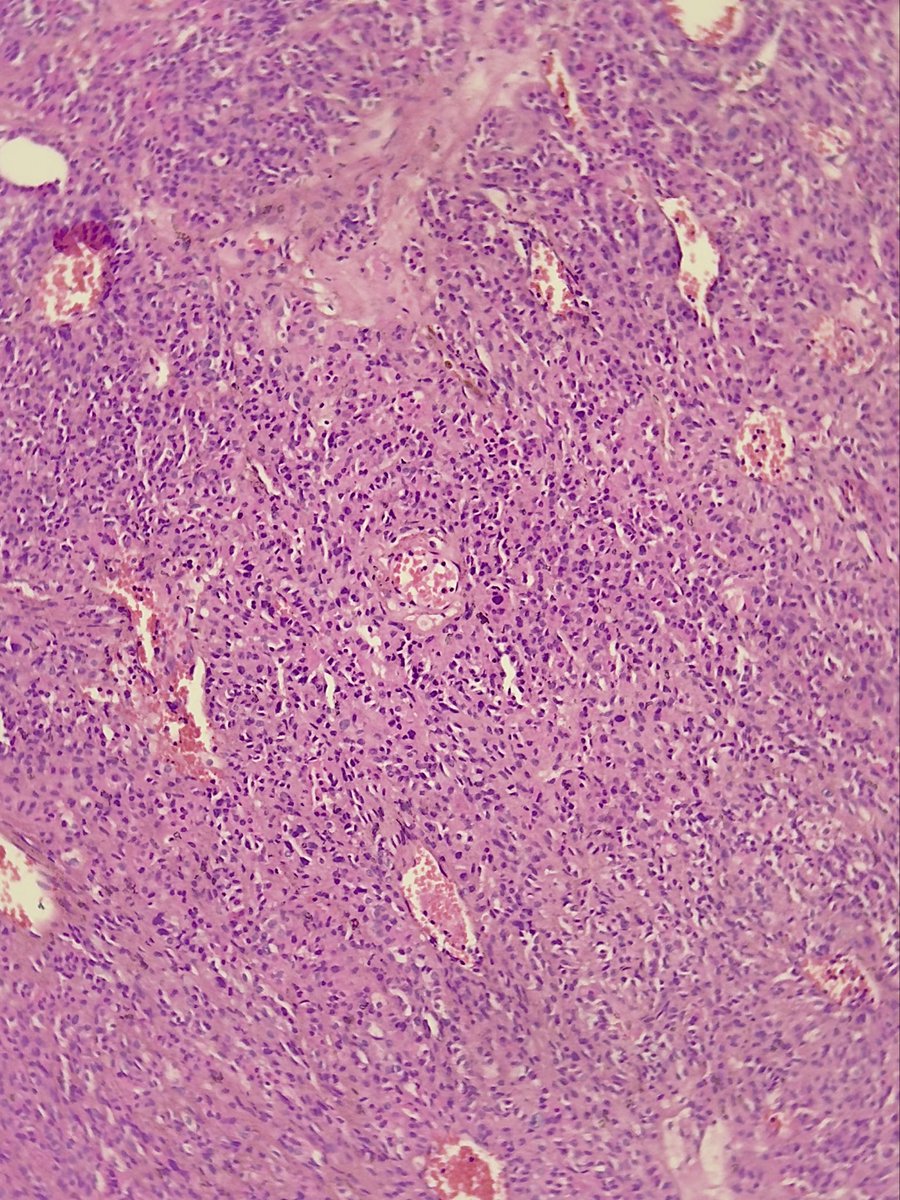

Kindly share your thoughts on this: Late 30s, About 4 years of recurring headache and worsening vision bilaterally. 👨🏾‍⚕️🔪-Well encapsulated huge suprasellar mass ?Pituitary macroadenoma No access to IHCs. #CNSPath #Neuropath #Endopath #Pathology

Late 30s, About 4 years of recurring headache and worsening vision bilaterally.

👨🏾‍⚕️🔪-Well encapsulated huge suprasellar mass ?Pituitary macroadenoma

No access to IHCs.